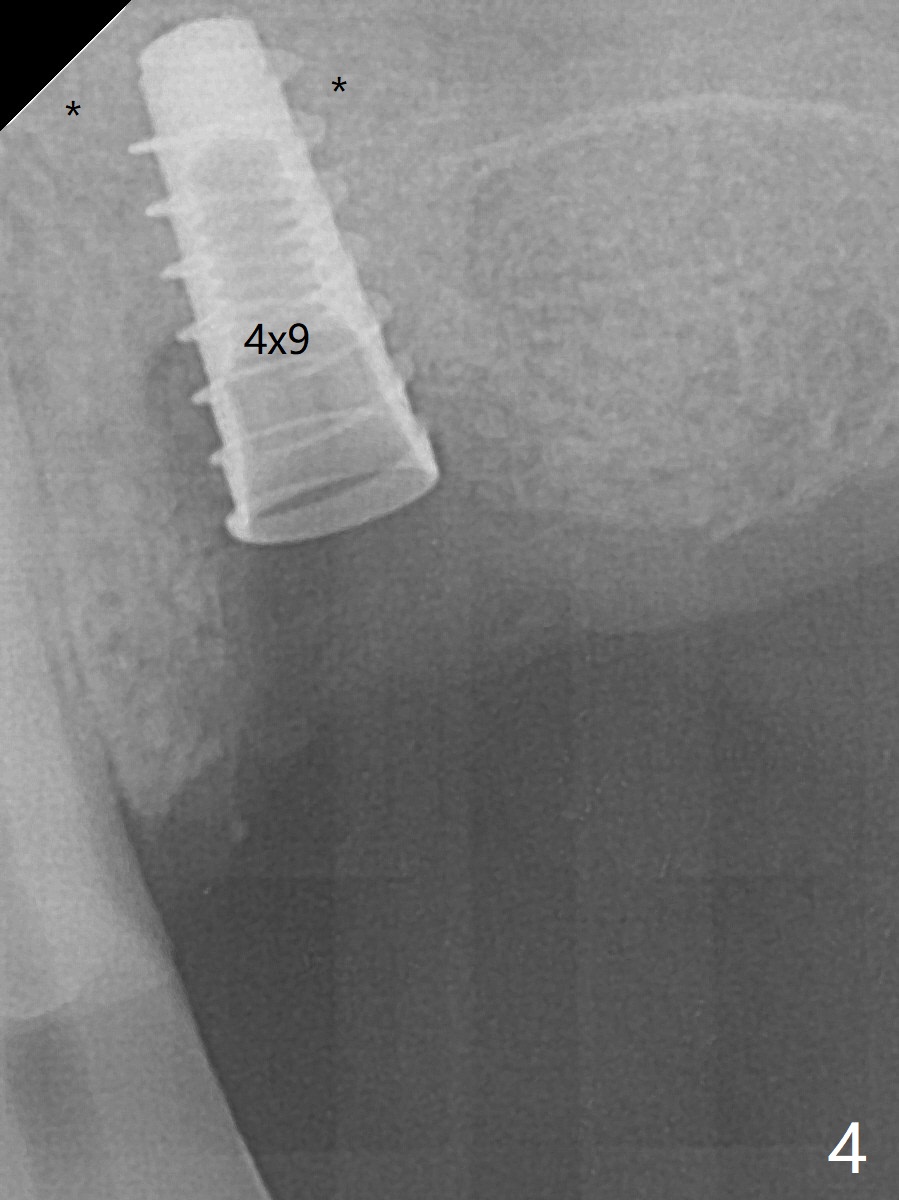

Five months post implant removal and bone graft, incision is made at #12. Osteotomy is being done with guide until 3.0x7.3 mm drill with 1 O-ring (palatal wall being thin), followed by 3.2x17-19 mm sinus round drills and 2.2x11.5 mm drill. After placement of 2 small loads of bone graft, a 4x9 mm dummy implant is inserted for sinus lift (Fig.1,2 *). By this time, the buccal plate is gone, while there is apparently the palatal periosteum. With more bone graft for sinus lift, a 4x9 mm final implant is placed with 30 Ncm (machine) and 4 mm subgingival (Fig.3,4 double arrows). Sticky bone (Fig.5,6 *) is applied around the coronal end of the implant and cover screw (S), followed by 2 pieces of PRF and 4-0 PGA suture. The sutures appear to have been dissolved and PRF membrane exposed 7 days postop (Fig.7,8 (smoker)). Four months postop, the wound heals except a small hole, which seems to be communicated with the underlying implant (Fig.9). The sinus lift remains (Fig.10 <), while bone loss appears to be present around the implant (Fig10,11 *). After placement of 5.5x4 mm healing abutment and before suturing, allograft is pushed into periimplant space (Fig.12, 13 *).